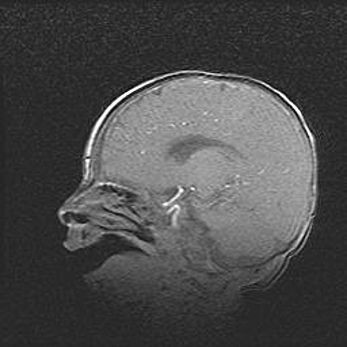

Неполная лизэнцефалия (пахигирия). Открытая гидроцефалия.

Возраст: 17 дней

Вес: 3110 г

Пол: мужской

Окружность головы: 33,5 см

Срок гестации: 35-36 недель

Лизэнцефалия—недоразвитие корковой пластинки и мозговых извилин в результате нарушения миграции нейронов коры. Поверхность мозговых полушарий гладкая. Микроскопически выявляется отсутствие нормальных слоев коры и скопление групп нейронов в подкорковом белом веществе.

Пахигирия—уменьшение числа вторичных извилин. В пораженном полушарии нервные клетки образуют толстый недифференцированный слой с неправильно расположенными нервными волокнами и группами гетеротопных клеток. Нервные клетки незрелые. Белое вещество истончено. При этом нередко аномально развит корково-спинномозговой путь.